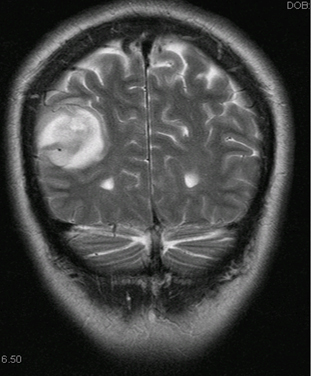

TC/ressonância nuclear magnética (RNM) de crânio: deve ser realizada se houver suspeita de hipertensão intracraniana, principalmente se os sintomas forem acompanhados por cefaleia intensa. Em neonatos e bebês pequenos, é preferível a ultrassonografia.[Figure caption and citation for the preceding image starts]: Tomografia computadorizada (TC) mostrando volume aumentado dos ventrículos laterais secundário a hidrocefalia não comunicanteDos acervos do Dr. R.A. Gomez-Suarez e Dr. J.E. Fortunato; usado com permissão [Citation ends].

[Figure caption and citation for the preceding image starts]: Tomografia computadorizada (TC) de crânio mostrando tumor cerebral parietotemporal à direitaDos acervos do Dr. R.A. Gomez-Suarez e Dr. J.E. Fortunato; usado com permissão [Citation ends].